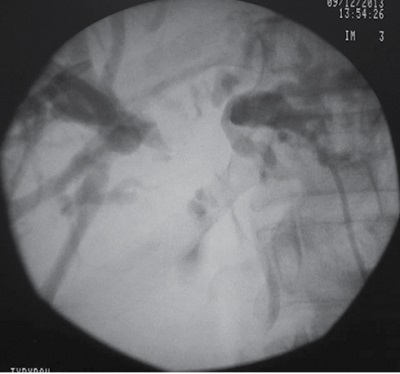

Одним из заболеваний билиарной зоны, сопровождающихся синдромом механической желтухи, является воротная холангиокарцинома, или опухоль Клацкина. В работе представлен клинический пример оценки функционального состояния печени у пациента с воротной холангиокарциномой с использованием метода клиновидной дегидратации. Пациенту с диагнозом «Опухоль Клацкина, тип III по BismuthCorlettе. Механическая желтуха» произведено первичное рентгенохирургическое пособие – раздельная наружная чрескожная чреспеченочная холангиостомия правого и левого долевых протоков под ультразвуковым и рентгенотелевизионным контролем.

В момент формирования первичного чрескожного доступа в желчевыводящие пути и в последующем каждые трое суток выполнялось исследование кристаллографических свойств желчи правой и левой долей печени с использованием метода клиновидной дегидратации. Полученные результаты показали, что в левой доле печени наблюдаются более тяжелые функциональные нарушения в сравнении с правой долей. Полученная информация с учетом клинико-лабораторных и инструментальных данных была использована при выборе последующей тактики ведения и оперативного лечения пациента. Представленное клиническое наблюдение указывает на эффективность применения метода клиновидной дегидратации в динамической оценке метаболизма печени и его перспективное использование в алгоритме лечения пациентов с механической желтухой на фоне воротной холангиокарциномы.